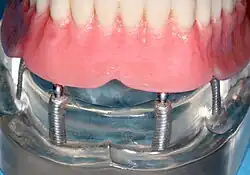

Implantátem držená protéza

Snímatelná zubní protéza s implantáty (také implantáty podporovaná protéza[14]) je odnímatelná náhrada, která nahrazuje zuby pomocí implantátů ke zlepšení podpory, retence a stability. Nejčastěji se jedná o kompletní zubní náhrady (na rozdíl od částečných), které se používají k obnově bezzubých zubních oblouků.[9] Zubní náhradu lze odpojit od implantátových opor tlakem prstu nositele.

Protetické postupy u snímatelných zubních náhrad

Při nošení snímatelné zubní náhrady mohou být fixátory, které drží zubní náhradu na místě, vyrobeny buď na zakázku, nebo jako "hotové" (skladové) abutmenty. Při použití zakázkových fixátorů se umístí čtyři nebo více implantáty, pořídí se otisk implantátů a v zubní laboratoři se vytvoří zakázková kovová tyč s nástavci, která drží zubní náhradu na místě. Výraznou fixaci lze vytvořit pomocí více nástavců a použitím polopřesných nástavců (například čepu malého průměru, který se protlačí skrz zubní náhradu do tyče), což umožňuje malý nebo žádný pohyb zubní náhrady, která však zůstává snímatelná.[14]:s.33–34 Stejné čtyři implantáty nastavené pod takovým úhlem, aby rozkládaly okluzní síly, však mohou bezpečně udržet fixní zubní náhradu na místě se srovnatelnými náklady a počtem zákroků, což nositeli zubní náhrady poskytne fixní řešení.[45]

Alternativně se k upevnění zubní náhrady používají zásobní abutmenty s použitím samčího adaptéru připevněného k implantátu a samičího adaptéru v zubní náhradě. Dva běžné typy adaptérů jsou držák ve stylu koule a zásuvky a adaptér ve stylu knoflíku. Tyto typy zásobních abutmentů umožňují pohyb zubní náhrady, ale dostatečnou retenci, která ve srovnání s běžnými zubními náhradami zlepšuje kvalitu života nositelů zubních náhrad.[46] Bez ohledu na typ adaptéru bude samičí část adaptéru, která je umístěna v zubní náhradě, vyžadovat pravidelnou výměnu, avšak nezdá se, že by počet a typ adaptéru ovlivňoval spokojenost pacientů s protézou u různých snímatelných alternativ.[47]